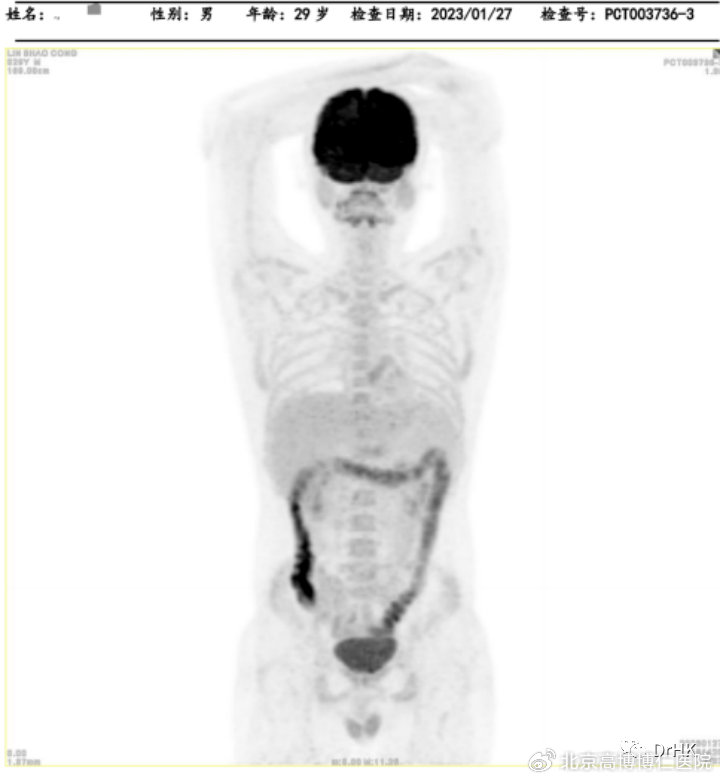

PET-CT:Deauville 评分5分。(1)肝脏累及,大小约3.2*2.6*3.7cm,最大SUV值22.4; (2)脑部:右侧颞叶深部、基底节区稍低密度灶,结合MRI图像,考虑淋巴瘤累及;(3)全身多发骨(双侧肩胛骨、锁骨、肋骨、胸骨、骨盆骨、脊椎骨)多发骨质吸收、破坏改变,部分区域骨质密度增高,以左侧髂骨为著;(4)左侧臀大肌,范围约1.2*1.6*1.5cm,最大SUV 12.4。

随后患者定期随访,分别于移植后半年、一年完善影像学评估,令人欣慰的是患者目前一直保持完全缓解状态。PET如下图所示:

(移植后半年影像学评估)